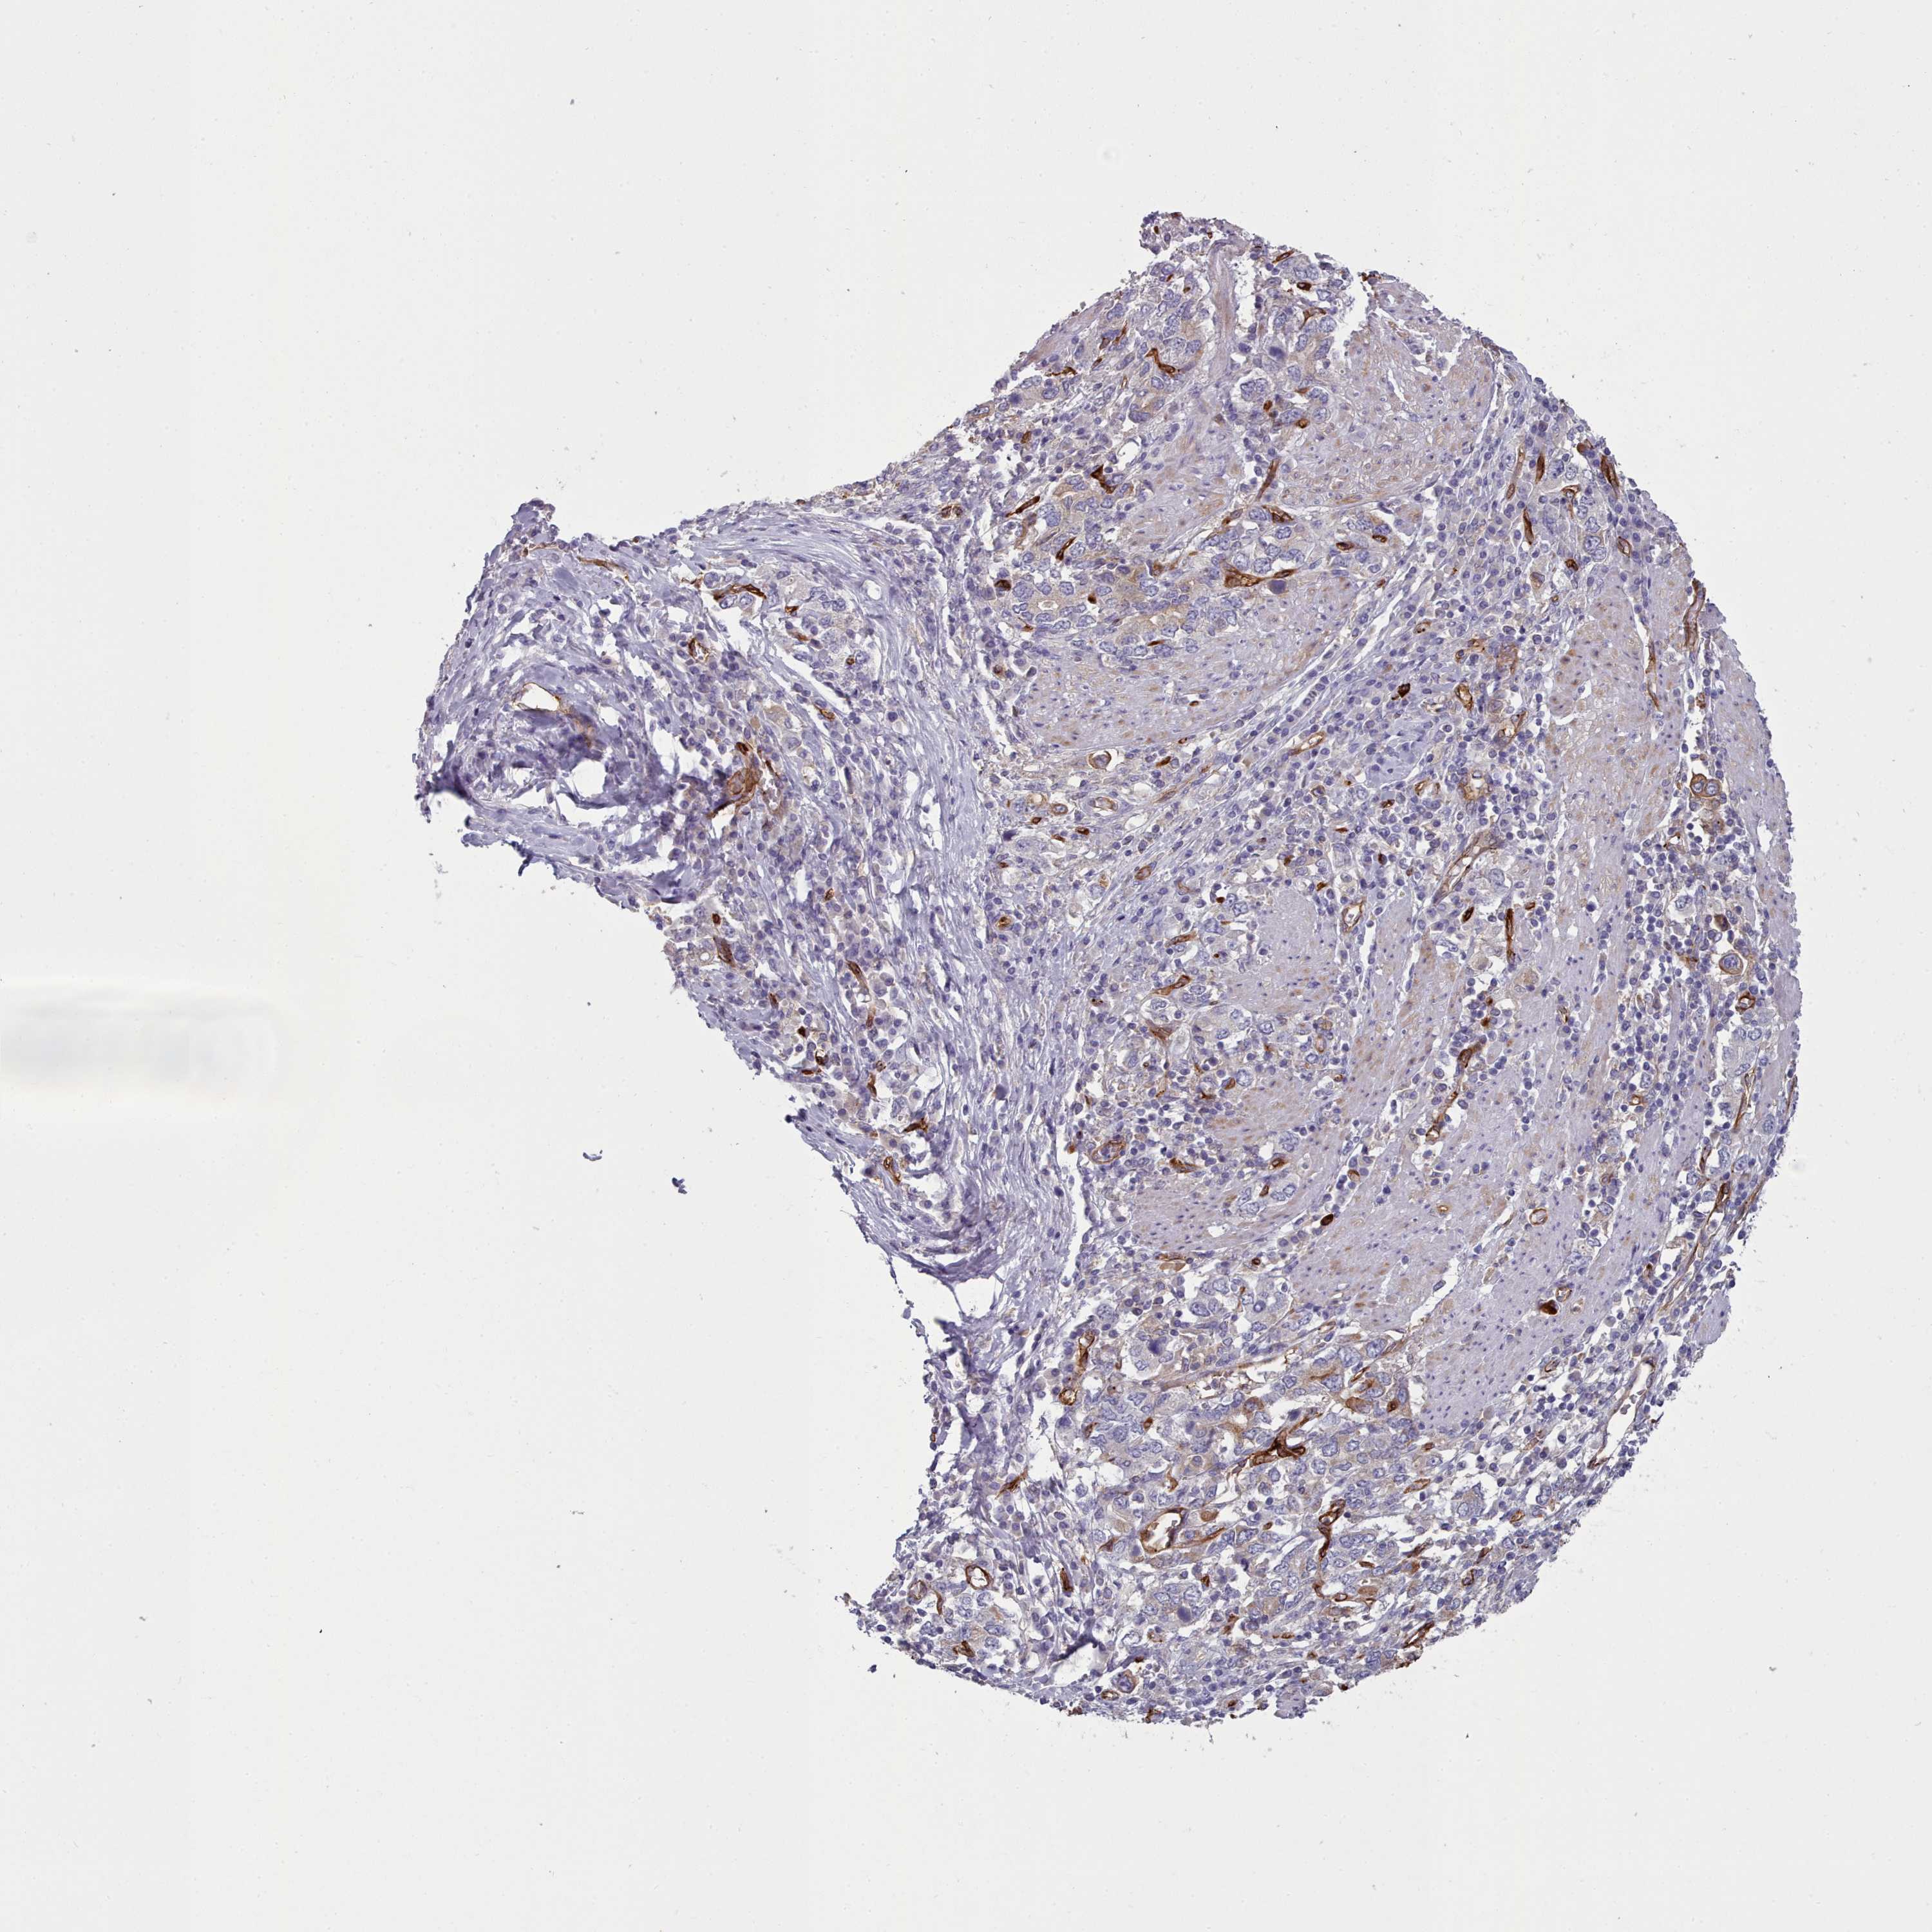

STOMACH CANCER - Protein expressioni

A mouse-over function shows sample information and annotation data. Click on an image to view it in a full screen mode. Samples can be filtered based on level of antibody staining by selecting one or several of the following categories: high, medium, low and not detected. The assay and annotation is described here.

Note that samples used for immunohistochemistry by the Human Protein Atlas do not correspond to samples in the TCGA dataset.

Antibody stainingi

Antibody staining in the annotated cell types in the current human tissue is reported as not detected, low, medium, or high, based on conventional immunohistochemistry profiling in selected tissues. This score is based on the combination of the staining intensity and fraction of stained cells.

Each image is clickable and will lead to virtual microscopy that enables deeper exploration of all samples and also displays staining intensity scores, fraction scores and subcellular localization as well as patient and tissue information for each sample.

Antibody HPA013712

Staining

High

Medium

Low

Not detected

Intensity

Strong

Moderate

Weak

Negative

Quantity

>75%

75%-25%

<25%

None

Location

Nuclear

Cytoplasmic/membranous

Cytoplasmic/membranous,nuclear

Adenocarcinoma, NOS